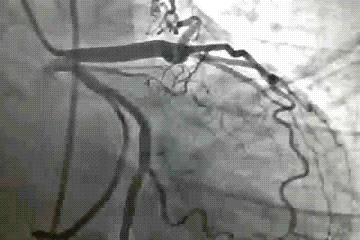

William Rashkind a cardiologist from Children’s hospital, Philadelphia in 1966 probably is the first person who thought it was indeed possible to use a wire and balloon as cardiac therapeutic intervention .When surgeons were groping in dark with sick cyanotic new borns with dTGV , He along with Miller executed their idea.

The procedure has since evolved with improving hardware and we are able to ferry a blade into the IAS for cutting .